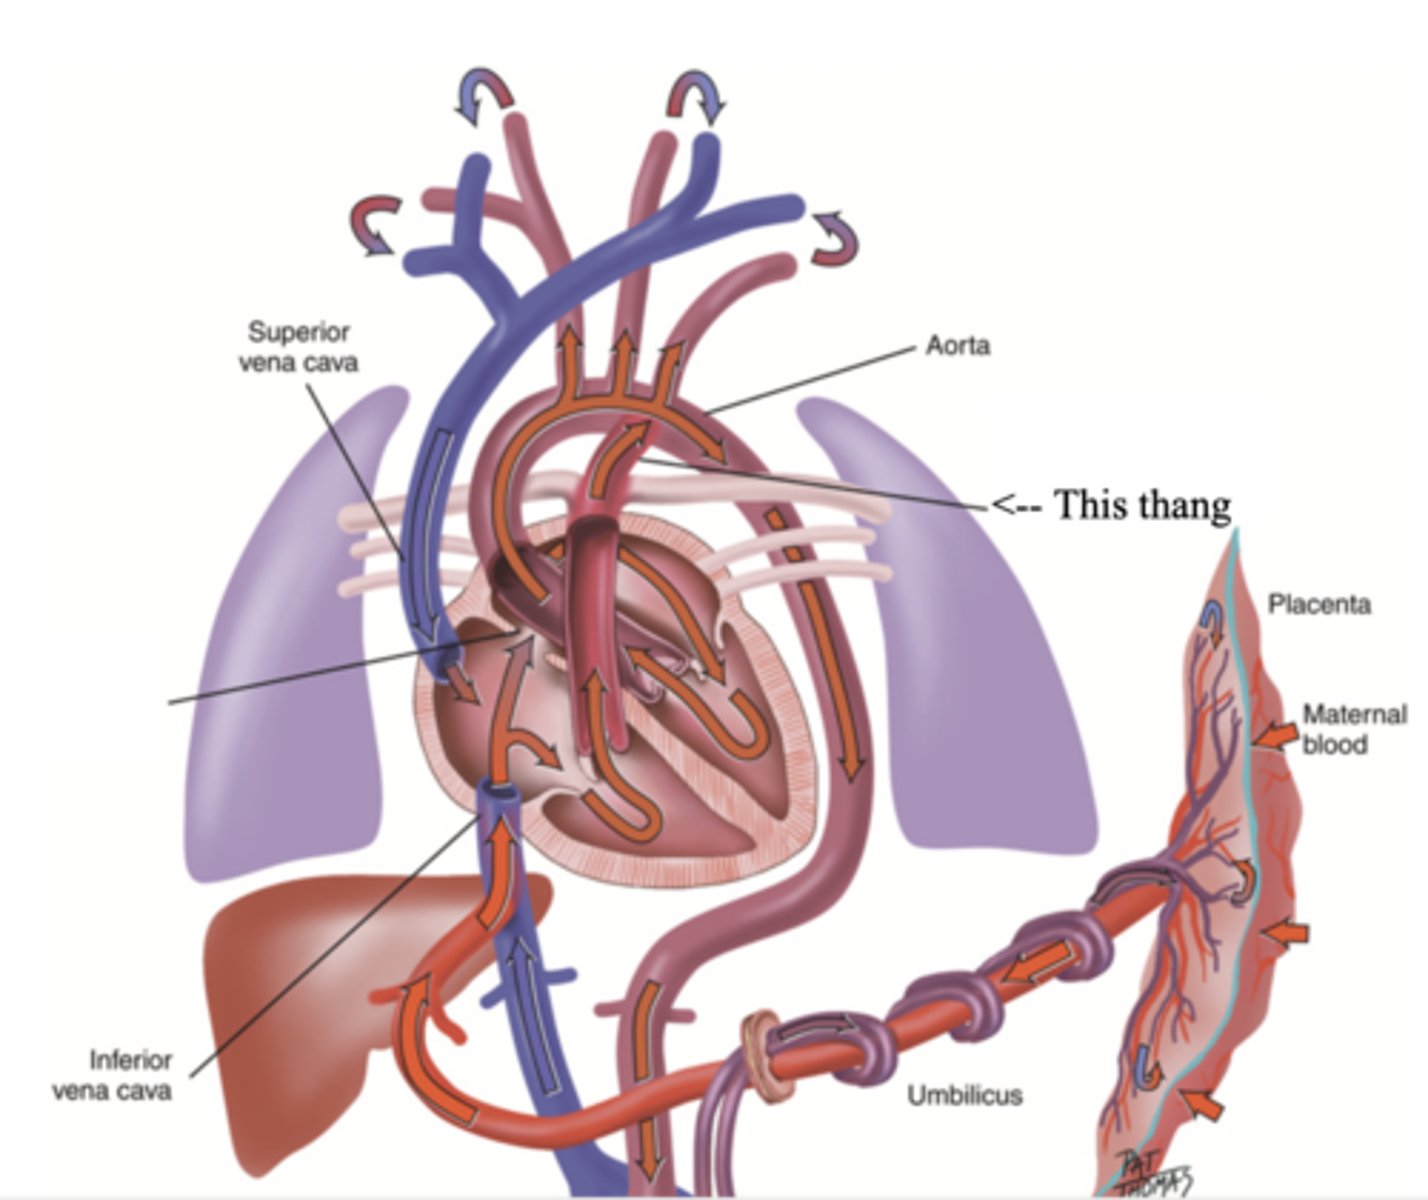

Foramen Ovale

A hole that connects the two atria in the fetal heart

Ductus Arteriosus

A blood vessel in a fetus that bypasses pulmonary circulation by connecting the pulmonary artery directly to the ascending aorta

Developmental Heart Considerations for Pregnant Women

- Increase in blood volume

- Increase in stroke volume

- Increase in cardiac output